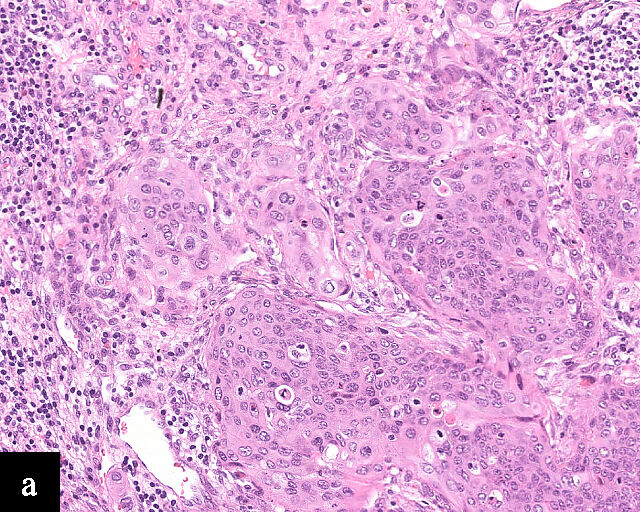

1

Histological sections of HPV-associated carcinoma of the cervix. Squamous cell carcinoma (magnification ×40; a,b) and adenocarcinoma (magnification ×20; c,d), shown with H&E stain (a,c) and p16 immunohistochemistry (b,d).